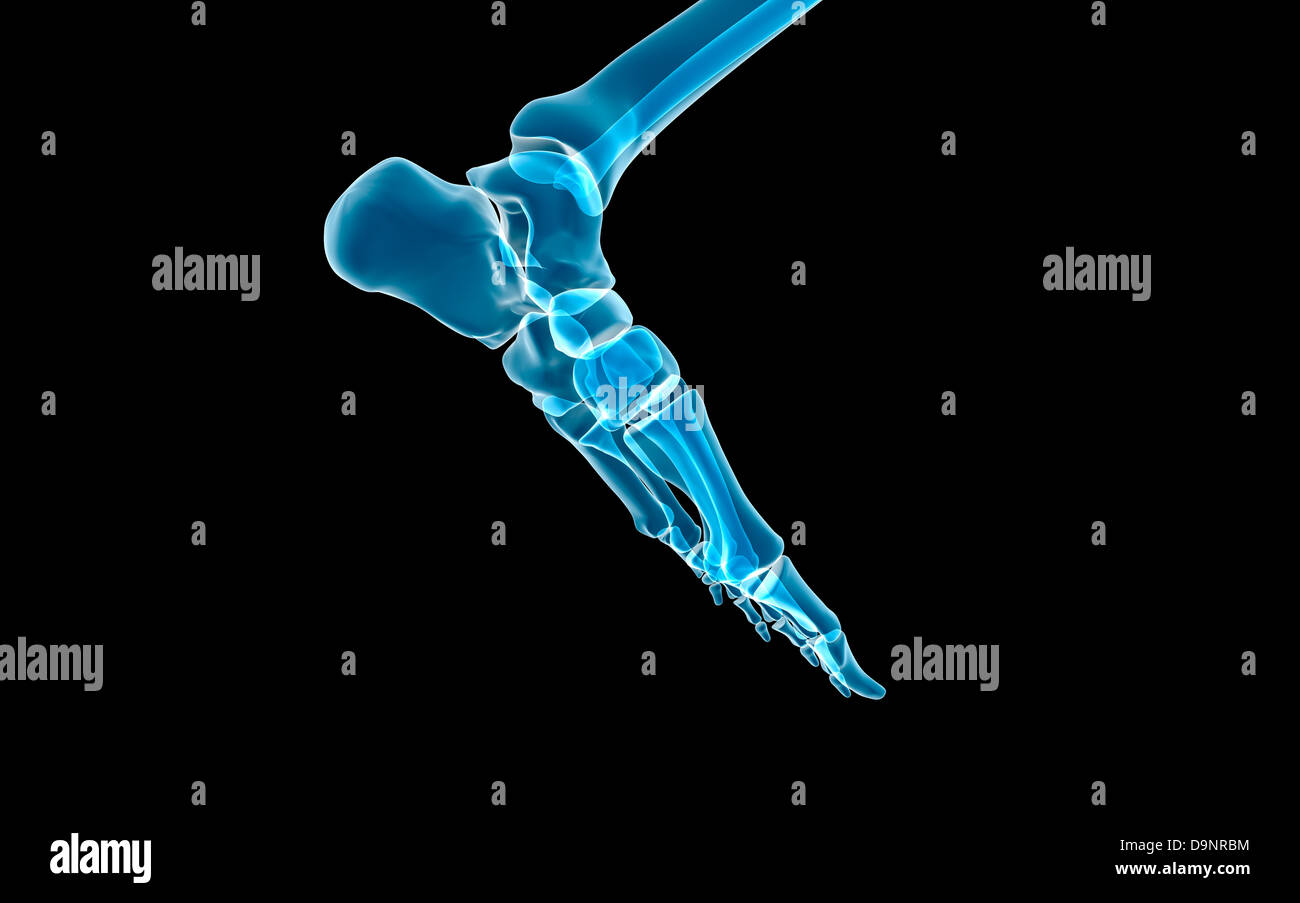

RF2GMNAX6–Vue latérale externe du squelette d'un pied humain articulé, avec la partie distale du tibia et du péroné montés sur un fil. Concept anatomique